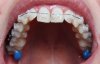

Ausgangslage: Deckbiss, also Tiefbiss mit nach innen gekippten OK-Schneidezähnen, wodurch auch das UK etwas zu weit hinten ist. Ein paar etwas verdrehten Zähnen (OK: 2er rechts und links, UK: 1er und 3er rechts und links). Falsche Verzahnung rechts

Behandlung: Feste Zahnspange mit Keramikbrackets, wobei die Backenzähne selbstligierende Metallbrackets bekommen haben (das soll dort besser gehen). Anfangs Aufbisse, damit ich mir wegen dem tiefen Biss nicht auf die Brackets beiße, später dann Gummis um den UK nach vorne zu kriegen.

Im Anhang noch ein Foto der Ausgangslage und eines von heute, in beiden beiße ich (soweit's geht) zusammen. Man sieht den Wetterunterschied in der Bildqualität;)